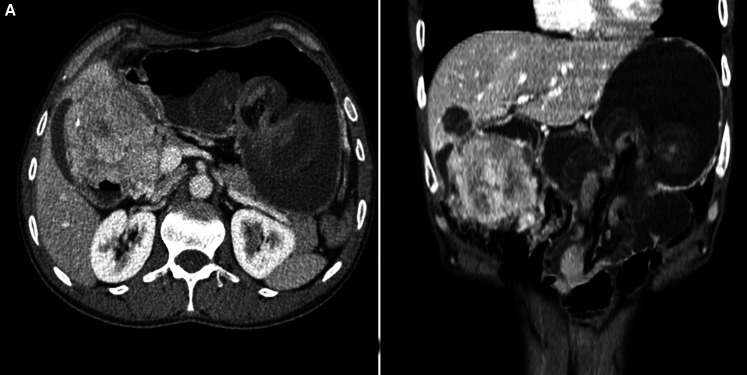

Jejunogastric intussusception (JGI) is a rare, potentially fatal complication of gastrojejunostomy following any gastric resection or gastric bypass surgery. Very less no of cases have been reported to date in the literature, with a very low incidence of <0.1%. Early recognition of JGI followed by prompt intervention is necessary to avoid any serious complications of gut gangrene or even possible death. It carries a mortality rate of approx. 10% of patients subjected to early intervention within 24 hours as compared to 50% in cases where surgery was delayed for more than 48 hours. The usual presenting complaints include a triad of palpable epigastric mass, hematemesis, and epigastric pain with only 50% of patients having this classical presentation. We here, report a middle-aged male with JGI which was diagnosed and managed at our center with emergency surgical intervention.